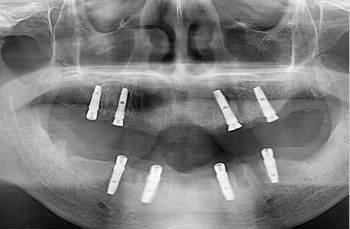

目前修復結果好一些,價格也比較貴一些的種植體主要有德國Friadent、美國3I種植、美國Bicon、瑞士ITI、瑞典Nobel Guide等,而比較便宜的是韓國的種植體,特別是韓國DIO、韓國奧齒泰等種植系統,只算種植體的價格一般在數千元左右就可以。